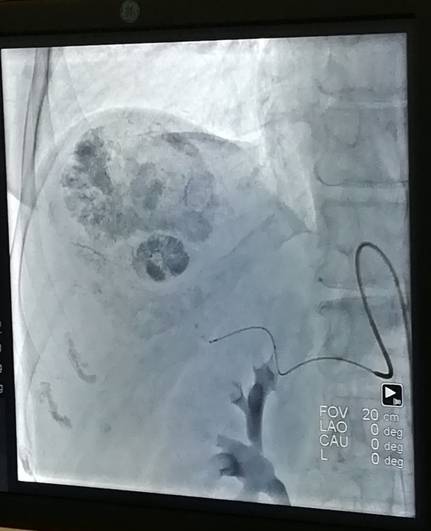

Хирурги ФСНКЦ ФМБА России внедряют технику химиоэмболизации для лечения рака печени. Этот способ подразумевает локальное лечение опухоли с минимальным воздействием на остальной организм.

Для этого врачи специальным препаратом блокируют артерию, питающую опухоль. Этот способ лечения имеет существенные преимущества перед другими хирургическими методами.

Химиоэмболизация меньше травмирует организм в целом, она позволяет лечить неоперабельные опухоли и использовать лекарства более высокой концентрации. Кроме того, этот метод минимально отравляет организм, при том, что действует на опухоль он дольше. Риски осложнений во время процедуры минимальны.

Данная техника применяется как самостоятельно, так и в сочетании с другими видами терапии. В Федеральном Сибирском научно – клиническом центре метод химиоэмболизации применили уже к 4 пациентам.